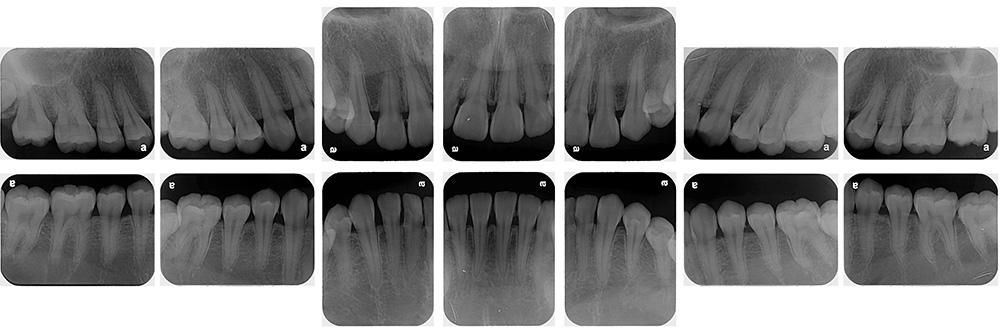

術前

術後

世代・性別

60代男性

主訴

歯ブラシで出血するので見てほしい

治療内容

ブラッシング指導、歯周基本治療、虫歯治療、根管治療、補綴治療

治療期間

6ヶ月

治療費

保険適応内

治療のリスク

治療後にしみる・痛みが出ることがある